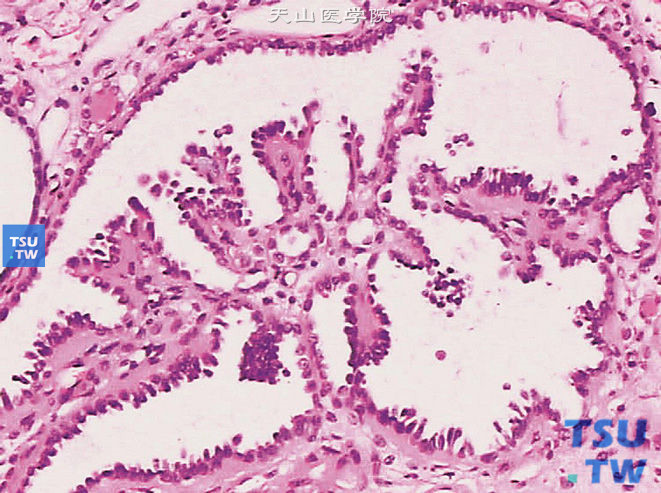

6图-1 肾乳头状腺瘤,结节状,边界清楚,位于肾皮质,紧邻肾被膜图-2 肾乳头状腺瘤,呈小管乳头状结构,细胞质稀少,胞核圆形或卵圆形,核仁不明显图-3 肾乳头状腺瘤。瘤细胞为大小一致的